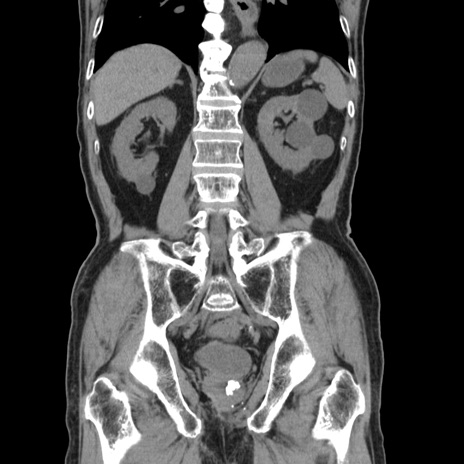

症例24(冠状断像)

【症例】80歳代男性

【主訴】左側腹部痛、嘔吐

【現病歴】本日早朝より左腹部に痛みあり。昼頃嘔吐認めたため、救急要請。

【既往歴】直腸癌(Mile手術)、胆摘

【身体所見】意識清明、BT 35.9℃、BP 221/93mmHg、SpO2 97%(RA) 、腹部:左ストーマ周囲に限局性の腹部膨隆あり。 膨隆部自発痛・圧痛あり・軟。

【データ】WBC 7700、CRP 0.09